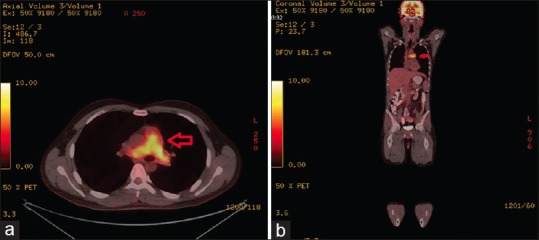

在急诊科,患者会出现很多症状。其中一个主要症状就是发烧,这可能是唯一的症状,我们的病人就是如此。不仅感染、药物、外伤等会引起发烧,就连未确定的癌症类型也会引起发烧。在本病例中,我们介绍了一名发热持续 3 周的 28 岁男性患者,入院诊断为肺动脉内膜肉瘤,一般被误认为是肺血栓栓塞症,以提高人们对这种致命癌症的认识。

In the emergency department, there are many symptoms patients present. One of the major symptoms is fever which could be the only symptom, as our patient had. Not only do infections, drugs, trauma, etc., cause fever, but also undetermined cancer types do. In this case, we are presenting a 28-year-old male coming with a 3-week duration of fever and being admitted with the diagnosis of pulmonary artery intimal sarcoma as generally misconceived with pulmonary thromboembolism, to raise awareness of this fatal cancer.